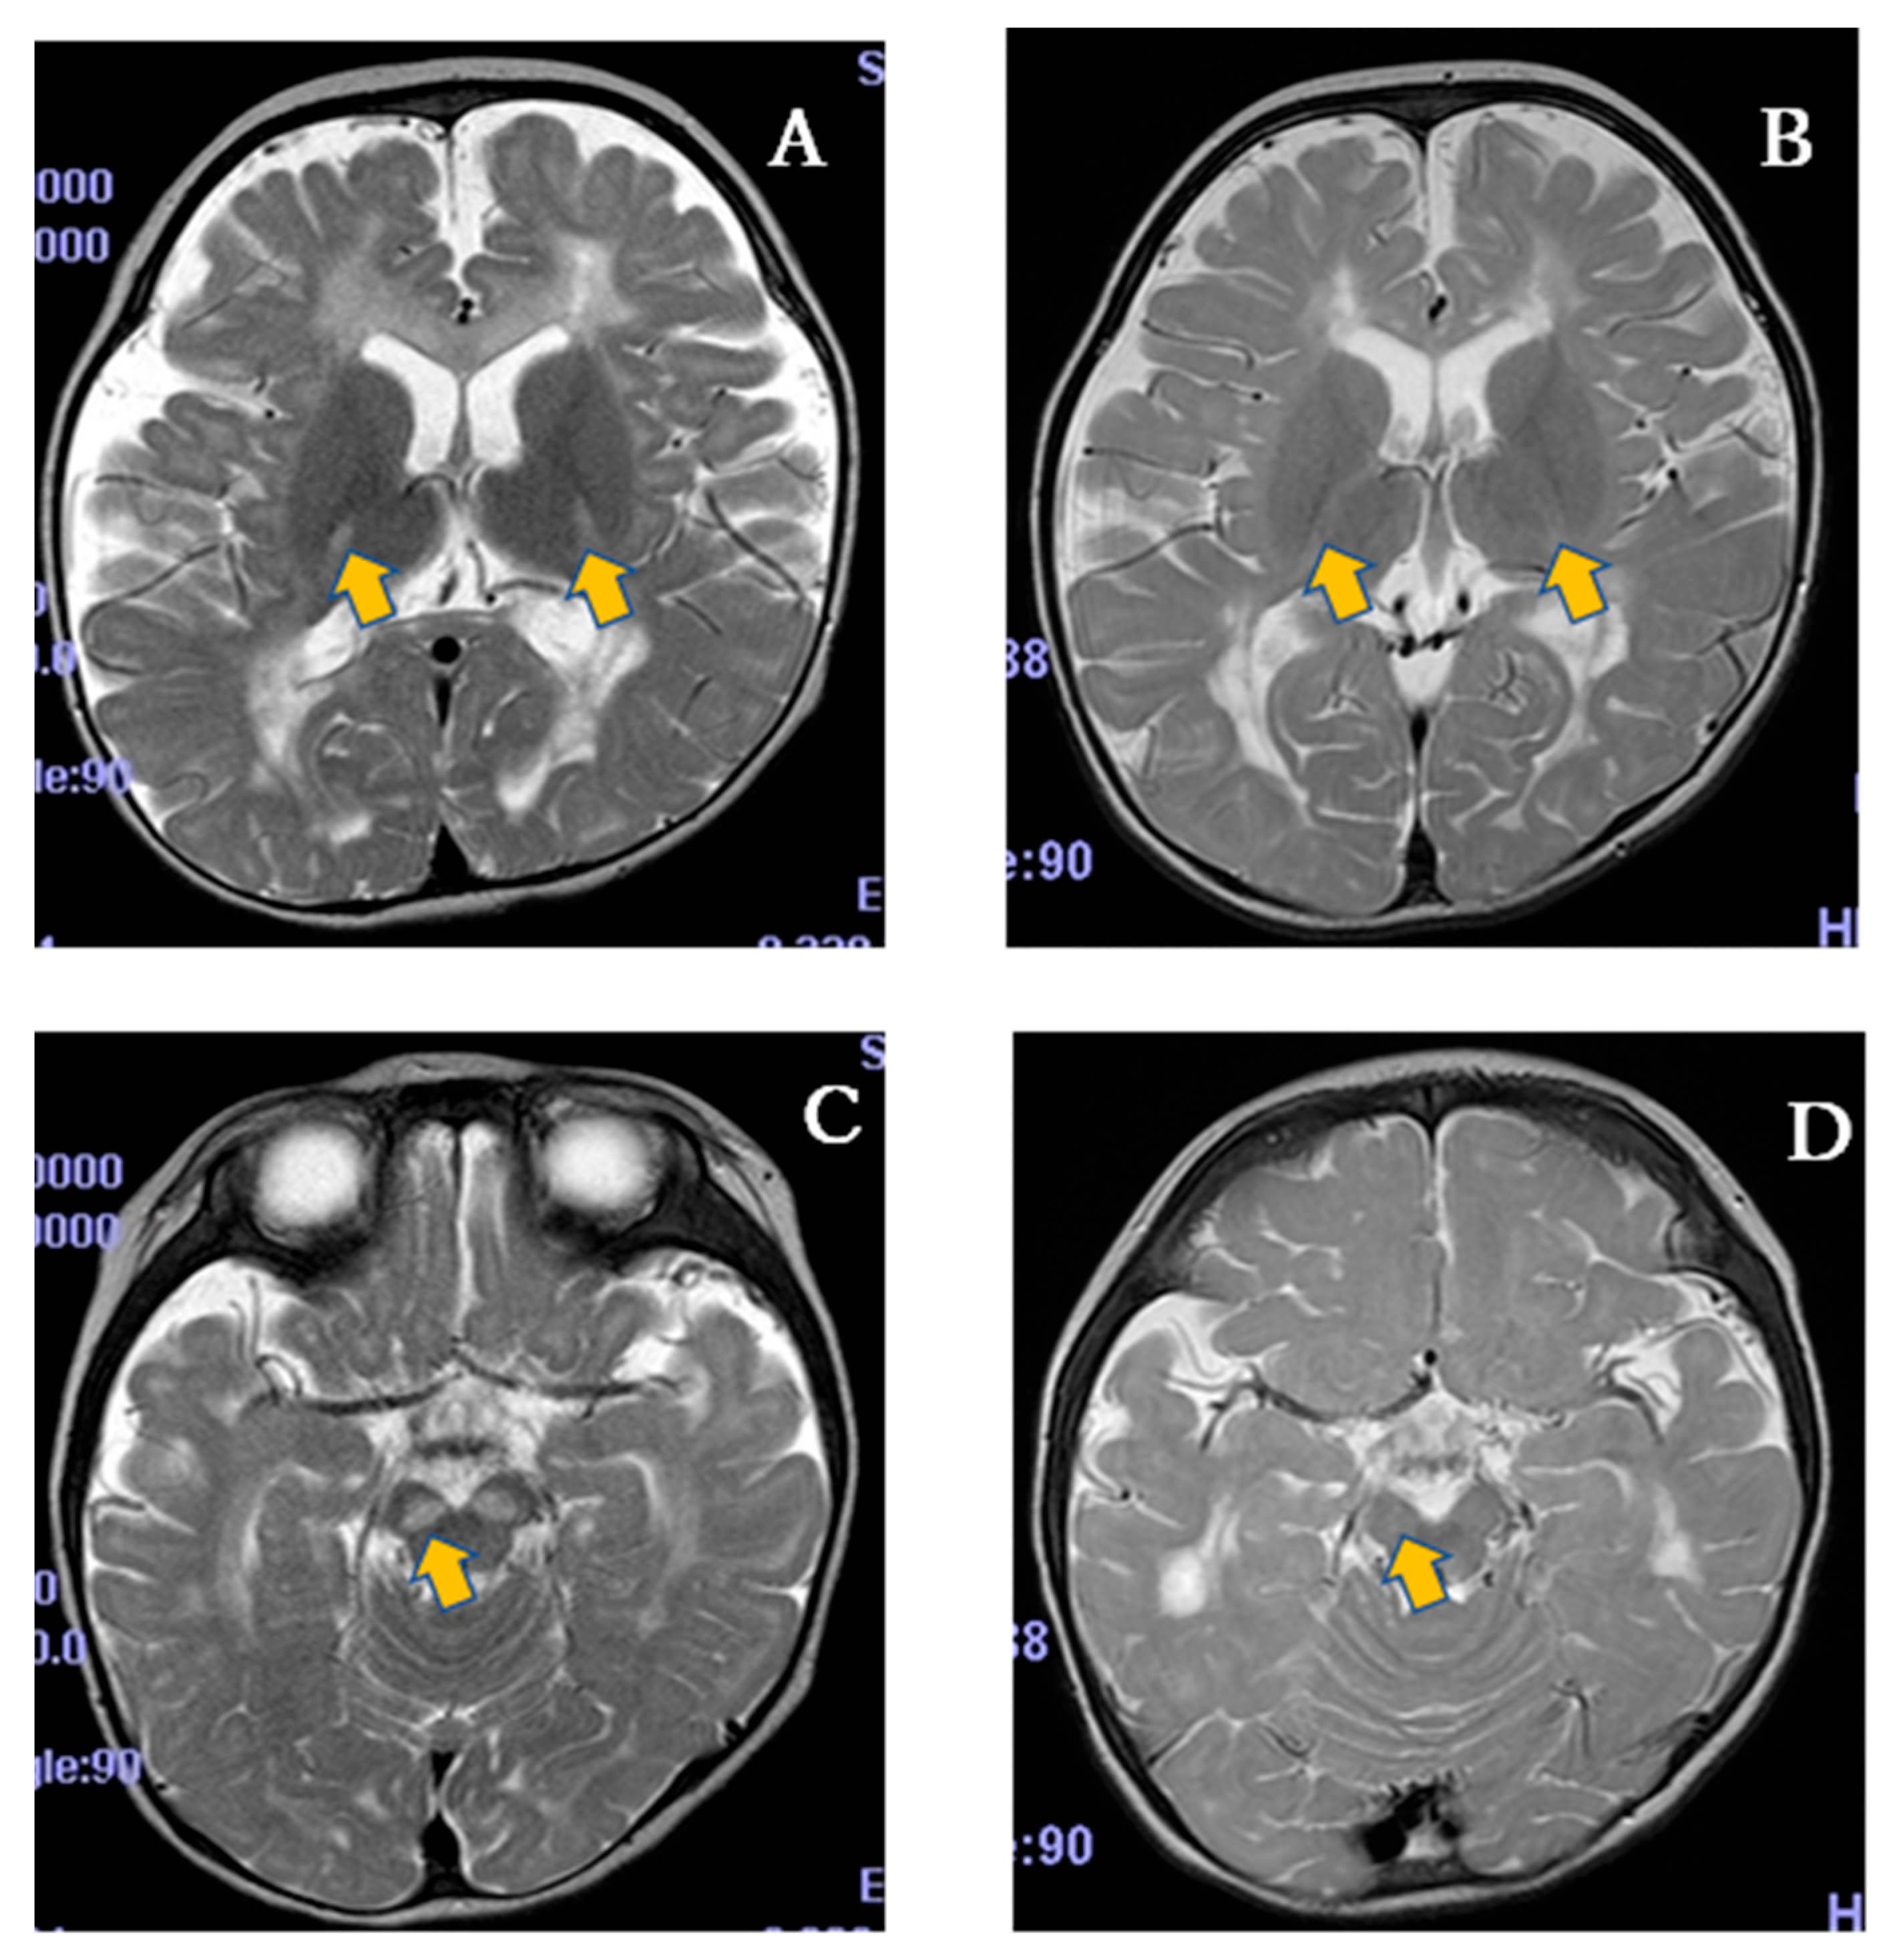

In addition to the clinical improvements suggested by the NPMDS scores, the radiological findings further support the potential efficacy of SPP-004. On the T2-weighted MRI of the PLA-04-01, a high signal intensity was observed in the bilateral basal ganglia (lateral thalamus) and brainstem (substantia nigra) before the clinical trial (Figure 5A,C), whereas these abnormal signals showed marked improvement after the trial (Figure 5B,D), suggesting a therapeutic effect. Such radiological improvement is particularly notable in LS, where the lesions in the basal ganglia are considered hallmark findings and typically persist or worsen over time in the absence of effective treatment. Therefore, the observed changes may provide visual and objective evidence of the therapeutic impact of SPP-004.

Figure 5.

Magnetic resonance imaging of the brain. PLA-04-01 at 19 months old before entering the trial (A,C) and at 36 months old after treatment with 5-ALA and SFC for 17 months (B,D). T2-weighted MRI showed high signal intensity in the bilateral basal ganglia (lateral thalamus) and brainstem (substantia nigra) before the trial (A,C), which decreased after the trial (B,D). The arrows indicate those legions before and after the trial.